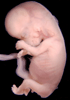

Carnegie Stage 23 (56 post-ovulatory days)

Most embryos at stage 23 are approximately 56-57 postovulatory days old and measure 23-32 mm in length. Distinguishing criteria for this stage include fusion of the eyelids at the medial and lateral margins, clear distinction of the subdivisions of the upper and lower limbs, the forearms appear at or above the level of the shoulders, the superficial vascular plexus of the head is very close to the vertex, and the external genitalia are well developed but not always sufficiently to distinguish the embryo's sex.

(NOTE: These specimens are late stage 23.)